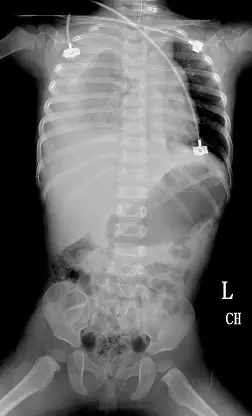

承上題【媽媽抱著1 歲半女童坐副駕駛座,爸爸因疲勞駕車自撞橋墩而被送至醫院急診,發現女童意識昏迷,對疼痛刺激稍微會縮手,血壓65/23 mmHg,心跳 153/min,呼吸 24/min,體溫 36.3℃,脈搏血 氧飽和度90%,目測體重約 10公斤,下列敘述何者錯誤?】,檢查全身無明顯出血及外傷,頭部電腦斷層無頭骨骨折及顱內出血,但仍意識不清,胸腹部 X 光如圖所示,輸注 packed RBC 100 mL後量測生命徵象,血壓114/53 mmHg,心跳 163/ min,呼吸 28/min,體溫36.7℃,脈搏血氧飽和度 90%,下列敘述何者錯誤?

- 影像為仰臥位前後投射胸腹部X光。可見:

- 氣管中線,已置入氣管內管;胃管走向正常。

- 右側胸腔整片高密度不透光,呈弧形凹陷邊緣(meniscus sign),符合大量胸腔積液。

- 無可見明顯肋骨骨折或骨折移位;中縱隔未顯著移位,顯示暫無張力性血胸。

- 左肺野透亮度正常;腹腔無明顯異常。

影像與臨床低血壓合併呼吸低氧提示右側血胸。